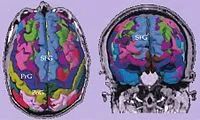

该图展示了从一个肿瘤患者得到的SPGR图像的皮质分割结果。